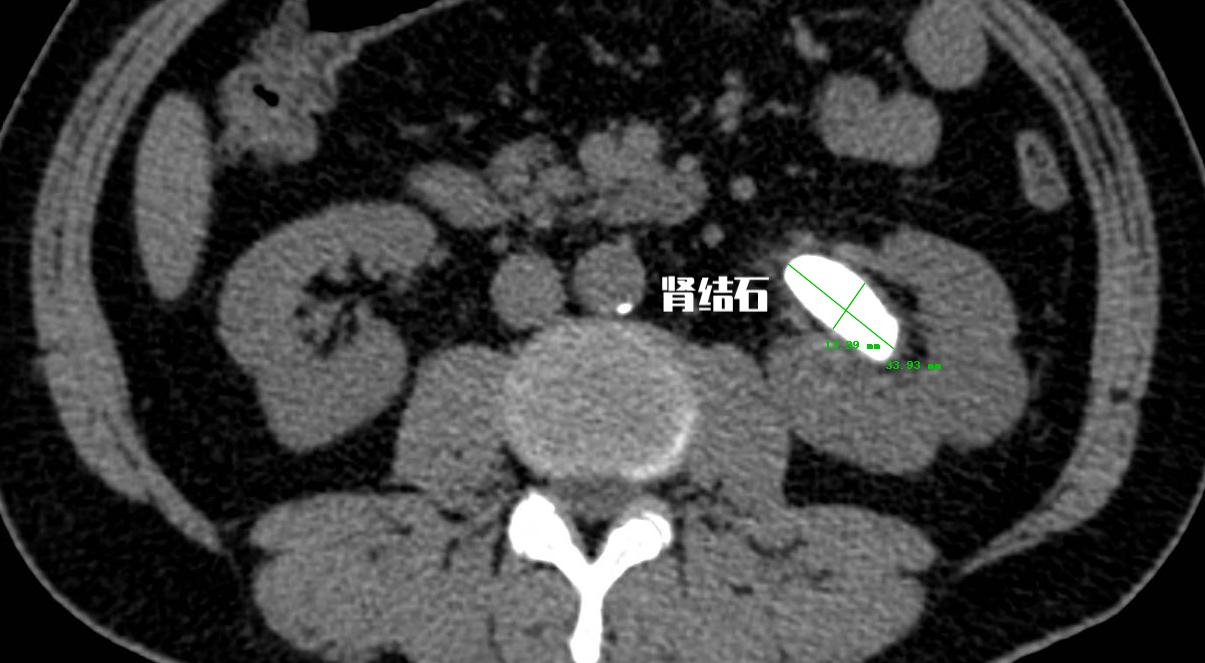

病例三:我这么大肾结石,选择哪种手术方式合适?

老张今年56岁,由于是自由工作,所以并没有规律的体检。上周因为有尿血的情况,于是到当地医院就诊, 查了CT提示左侧肾脏内有一长度约3cm结石。 那我应该选择用哪种手术方式来处理呢?